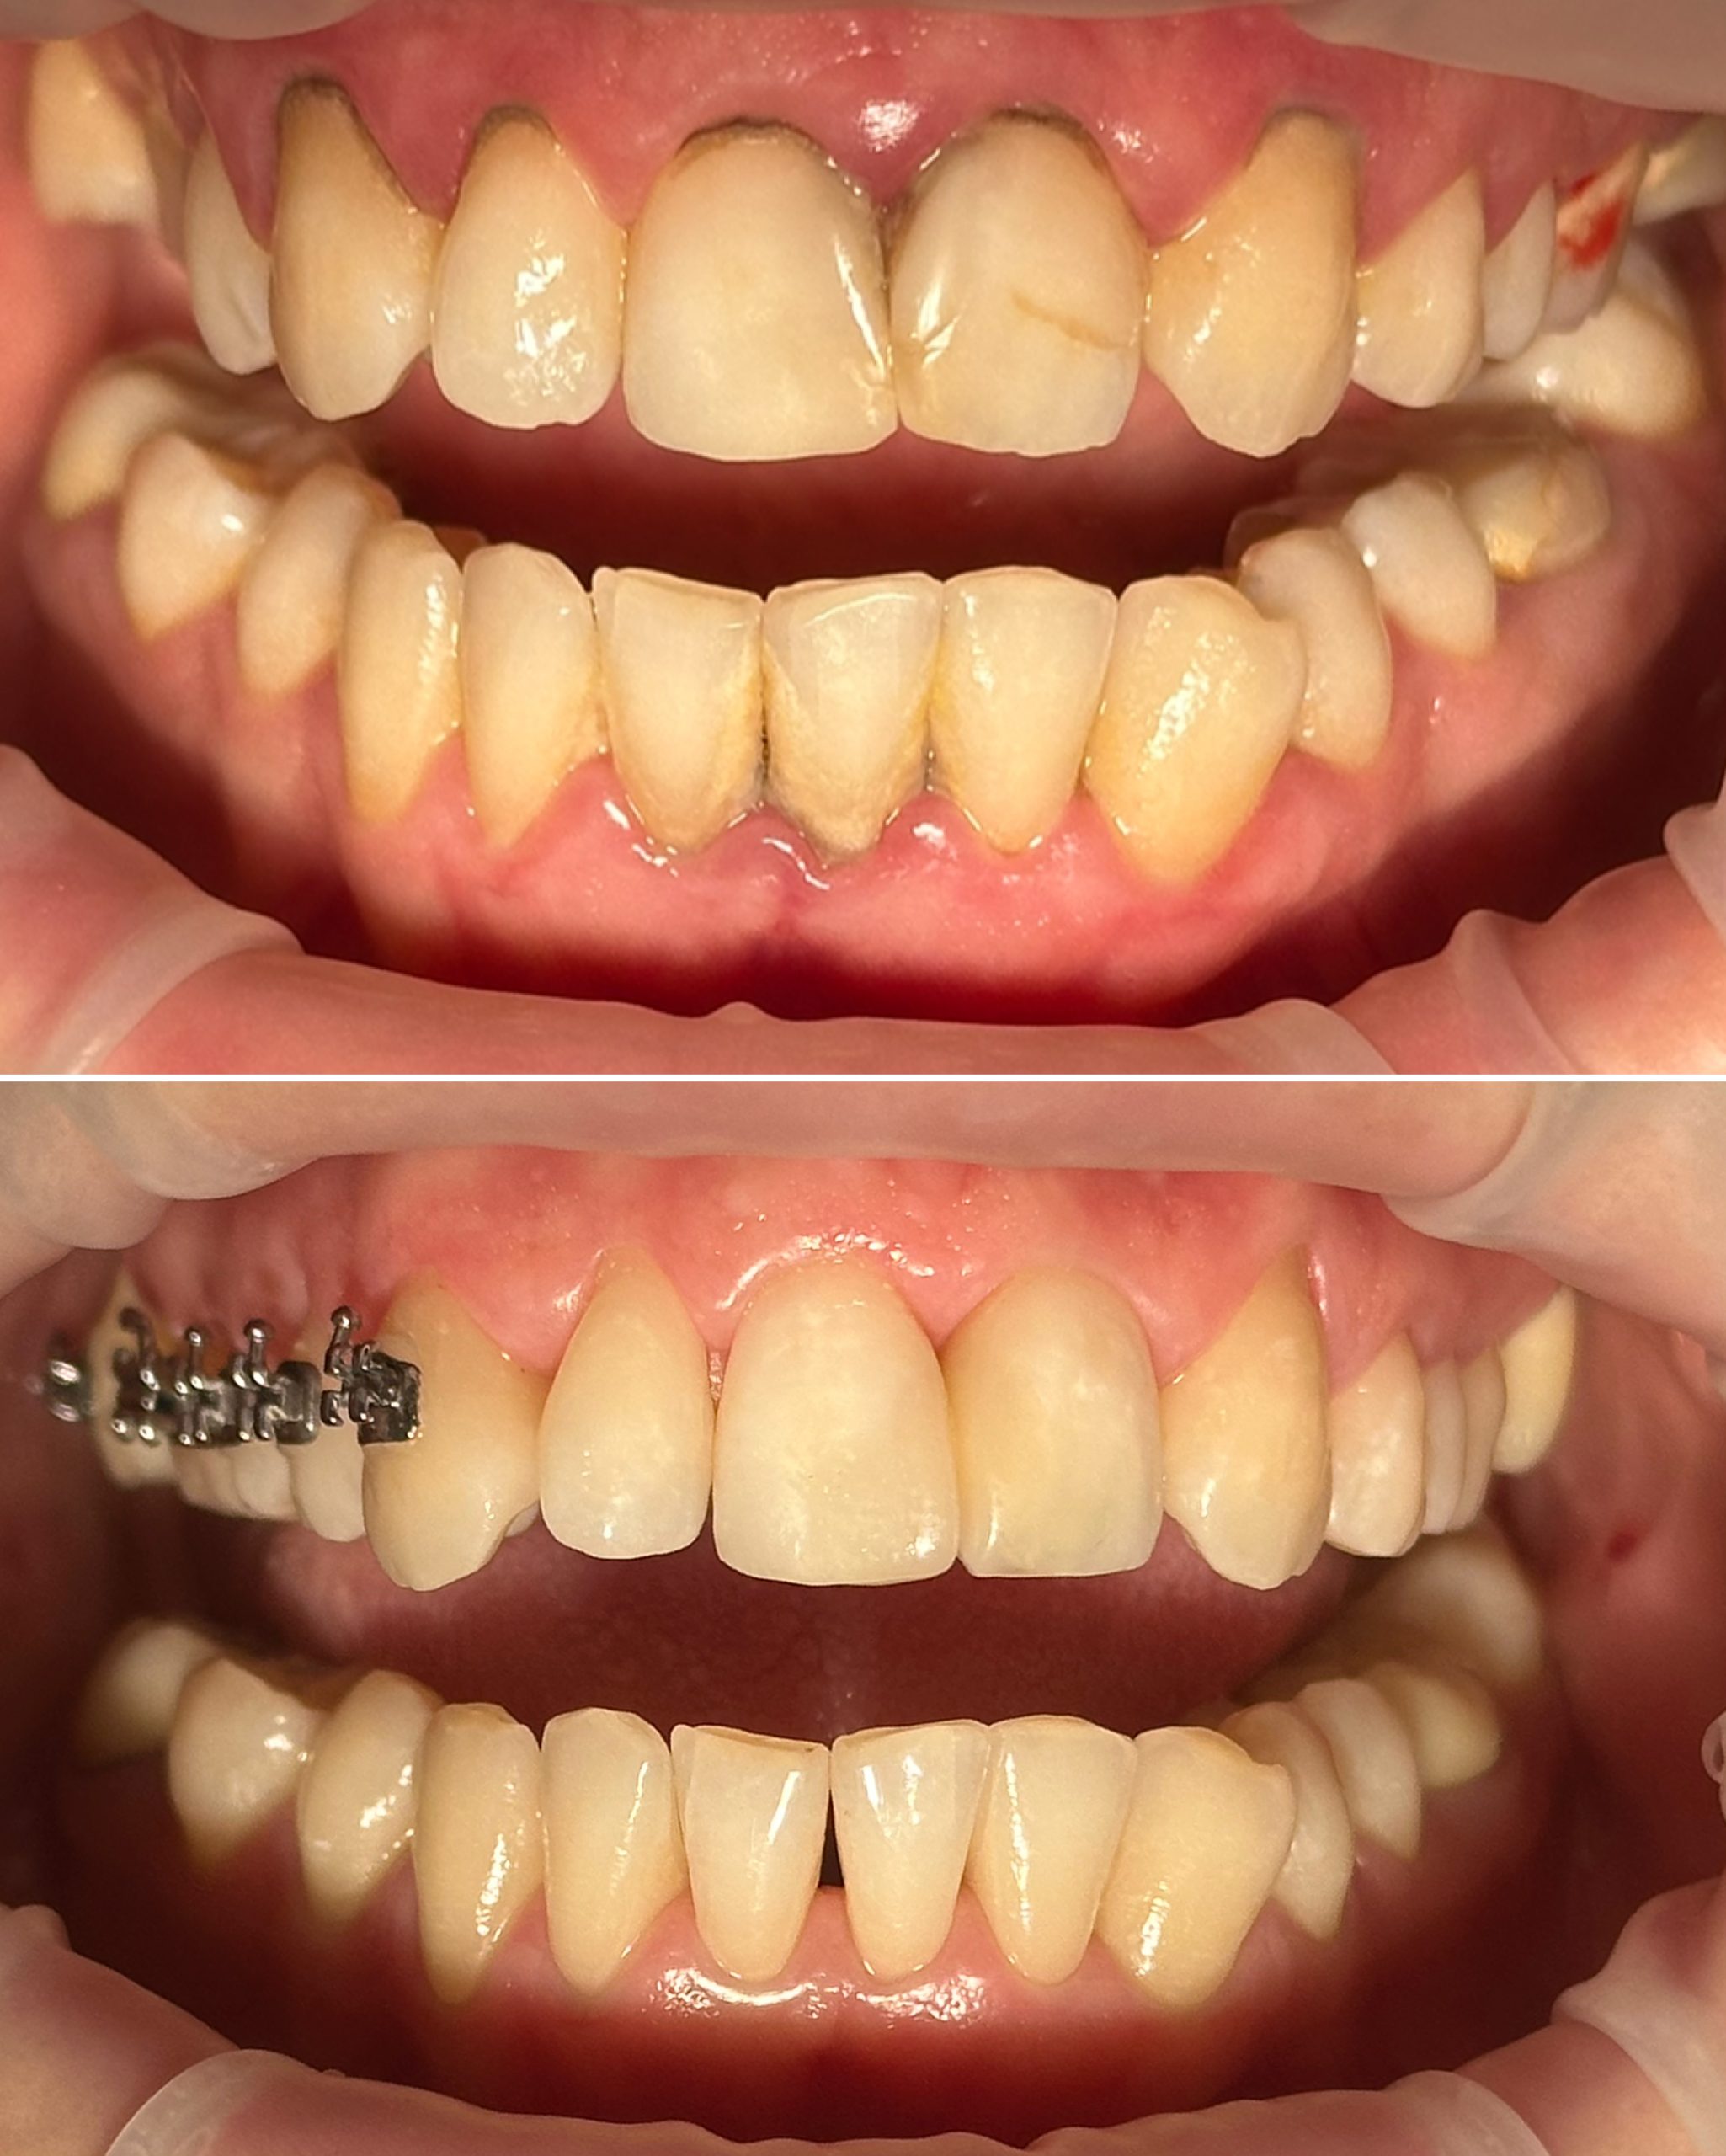

• Художественная реставрация фронтального и бокового участка зубов

2023 год – «Прямая композитная реставрация фронтальной группы зубов» Владимир Мальченко